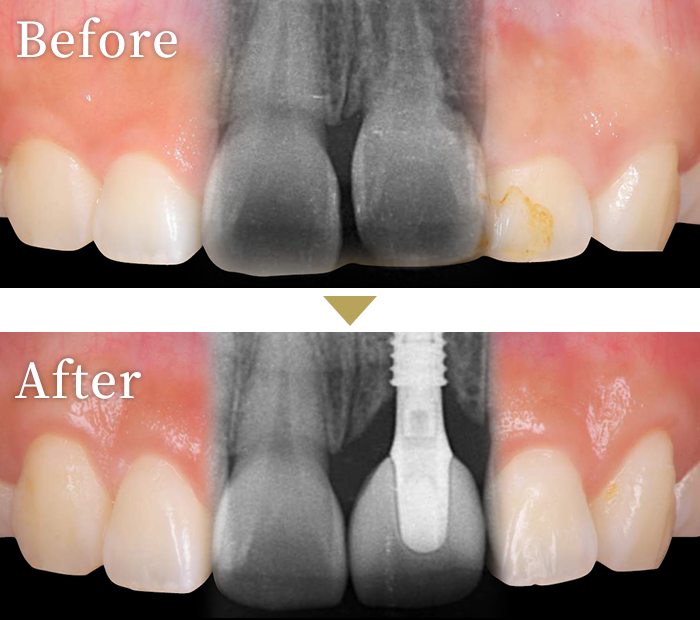

症例2

審美性獲得のため

歯茎の漂白も行った症例

インプラント症例3

主訴 左上の前歯がグラグラする。銀歯を白くしたい。

治療内容 左上中切歯と右上第一大臼歯にインプラントを埋入し、セラミックの上部構造を装着。

インプラント治療とは、別に審美性獲得の為、ガムブリーチングを実施。

治療期間 3ヶ月・5回

標準費用

(自費)

約65万円

リスク

副作用

• 治療には必ず手術を伴います。

• 重度の歯周病がある場合は、インプラント埋入後、脱離のリスクが高いです。

• 体質等によりインプラントと骨の定着が困難な場合があります。